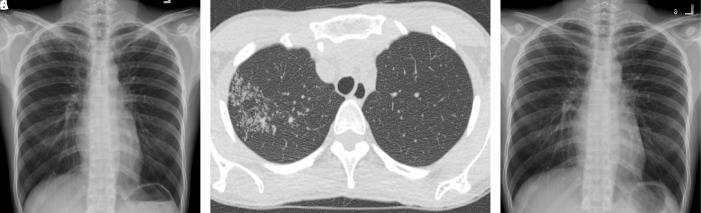

Results: Out of the 106 individuals identified with subclinical pulmonary TB, 84 met the criteria for inclusion in the analysis. The study found lower radiographic extent and increasing age were key attributes of culture-negative subclinical pulmonary TB. The odds ratios (95% confidence interval) were 7.18 (1.76 to 29.35) and 1.07 (1.01 to 1.13), respectively. They tend to have lower rates of bilateral involvement in both chest x-ray (8.5% vs. 32.0%, p=0.006) and computed tomography (15.4% vs. 42.9%, p=0.035). However, no other specific radiographic findings were identified.

Conclusions: People with culture-negative subclinical pulmonary TB were likely to have less radiographic -severity, reflecting early disease. Nevertheless, no radiographic patterns, except for unilaterality, were related to culture-negative subclinical pulmonary TB.